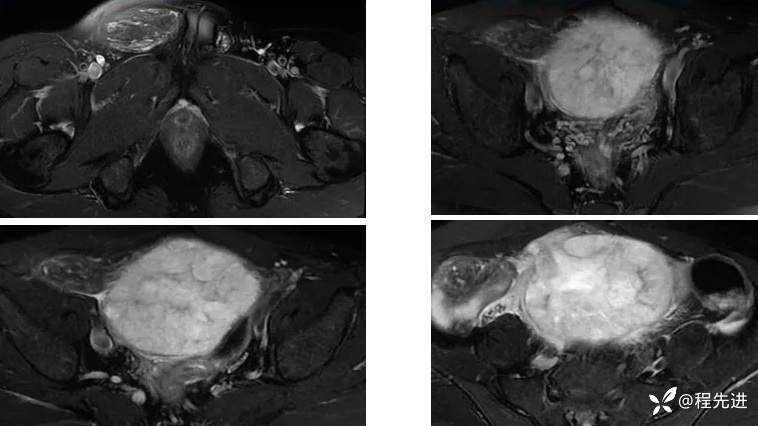

【腹盆】特别精彩病例|下腹痛20余天,男性病人腹腔巨大肿块该如何诊断

【患者信息】:男,41岁

【主诉】:下腹痛20余天

既往史:隐睾

肿瘤标志物:甲胎蛋白(AFP)>10000

增强: